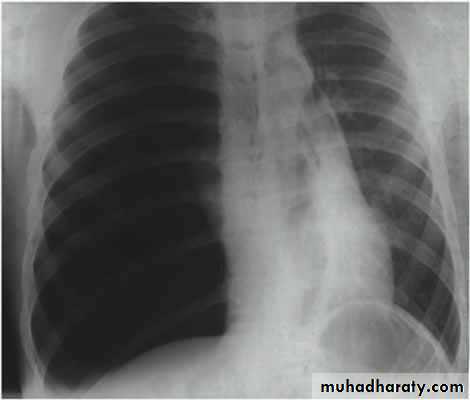

History; too shy to take of his shirt in the pool!